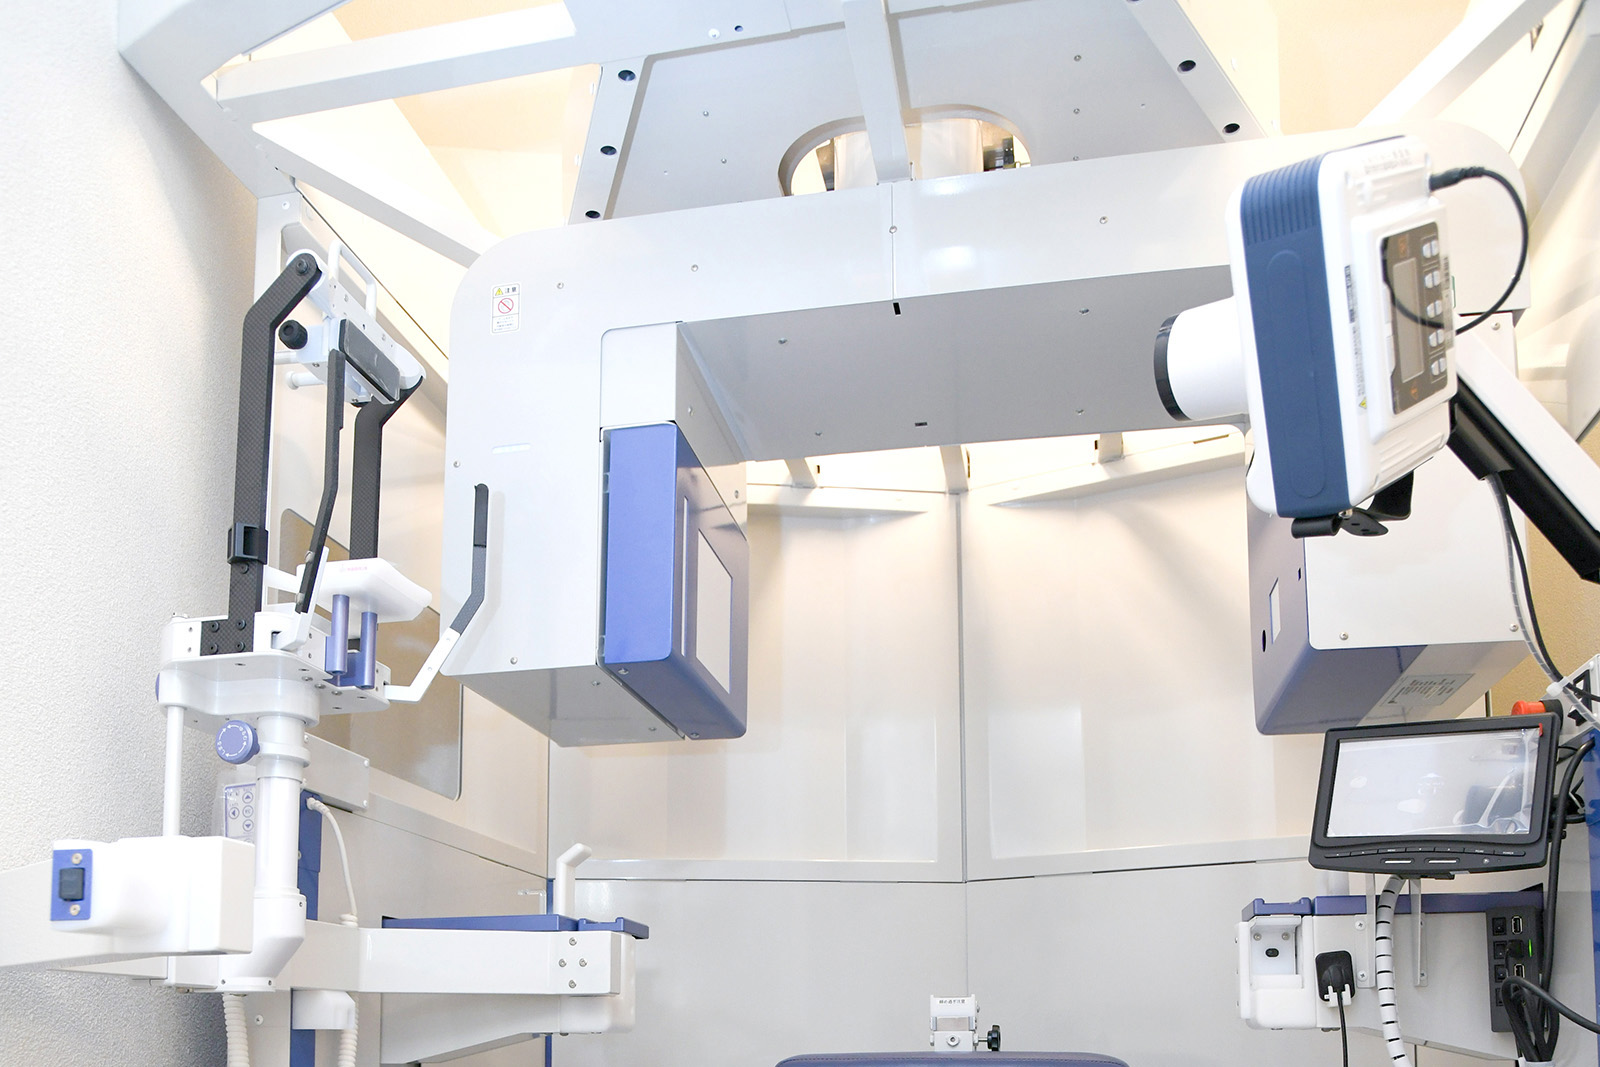

「CT分析」で顎の特徴を立体的に把握

患者さん一人ひとりの状態に合わせ、入れ歯づくりを進めるために、当院では「CT分析」を導入しています。

3Dモデルとして立体的に画像化しながら嚙み合わせのシミュレーションを行うことで、より精密な入れ歯の形状を考えることができます。